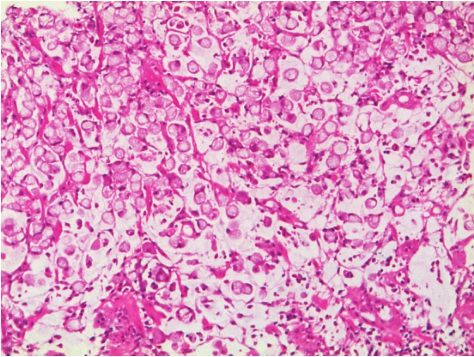

印戒细胞癌(signet-ring cell carcinoma)是胃癌的一种特殊病理类型,散在的或小团状的胞质内含有黏液的恶性肿瘤细胞占肿瘤细胞50%以上。因细胞内充满大量黏液,细胞核偏向一侧,外形酷似一枚戒指,故而得名。该病具有高侵袭转移的生物学特征,病程进展快,自然病程仅为3~6个月,较其他类型胃癌容易发生腹水转移。本病多见于中青年,特别是青年女性。

镜下观察:含有黏液的癌细胞占50%以上,不形成管腔或腺管,呈弥漫浸润性生长。胞质内黏液增多将细胞核挤压到细胞的一侧周边,使癌细胞呈印戒状(图3-14)。有时也形成黏液湖,细胞漂浮其中。肿瘤细胞有5种主要形态:①细胞核被细胞内黏液挤向一侧细胞膜,形成典型印戒样形态,阿辛蓝(pH 2.5)染色阳性;②细胞较小,核位于细胞中央,形态类似组织细胞样,缺乏分裂活性;③细胞小呈嗜酸性,胞质内含中性黏液颗粒,PAS染色阳性;④不含或含少量黏液的小细胞;⑤退行发育的细胞含或不含黏液。以上几种细胞混合排列,数量不一,形成不同的病理组织学形态,可以是花边状或纤细的梁状腺样结构,也可以呈带状或实性条索排列。

图3-14 印戒细胞癌

肿瘤细胞弥漫分布,胞质内充满淡蓝色黏液,将细胞核挤压至一侧,呈印戒样形态。